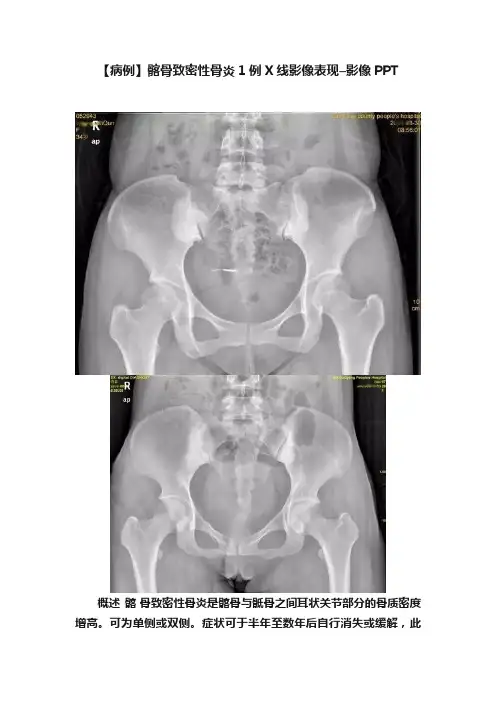

【病例】髂骨致密性骨炎1例X线影像表现–影像PPT

概述髂骨致密性骨炎是髂骨与骶骨之间耳状关节部分的骨质密度增高。

可为单侧或双侧。

症状可于半年至数年后自行消失或缓解,此

时髂骨的致密性改变并不随之消失。

X线表现在X线平片上可见靠近关节面处的髂骨皮质出现硬化性改变,骨质呈致密状,位于骶髂关节下1/2处,且多呈三角形;骶髂关节间隙整齐、清晰,关节面及骨质无破坏。

可单侧或双侧发病。